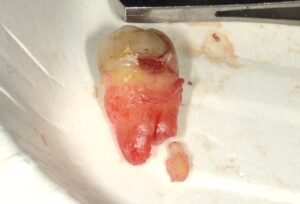

抜歯時に根が折れましたので折れた根も抜歯して

接合させてみて完全に根が抜歯できているか

確認します。